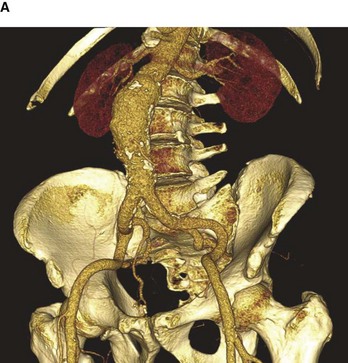

Kidney transplantation began in the United States in the 1950s. Since the first transplant, the major problem for kidney transplantation has been tissue rejection. A number of years have passed since this initial procedure and there have been significant breakthroughs in transplant rejection medicine. Renal transplantation is now a common procedure undertaken in patients with end stage renal failure.

Transplant kidneys are obtained from either living or deceased donors. The living donors are carefully assessed, because harvesting a kidney from a normal healthy individual, even with modern day medicine, carries a small risk.

Deceased kidney donors are brain dead or have suffered cardiac death. The donor kidney is harvested with a small cuff of aortic and venous tissue. The ureter is also harvested.

An ideal place to situate the transplant kidney is in the left or the right iliac fossa (Fig. 4.146). A curvilinear incision is made paralleling the iliac crest and pubic symphysis. The external oblique muscle, internal oblique muscle, transverse abdominis muscle, and transversalis fascia are divided. The surgeon identifies the parietal peritoneum but does not enter the peritoneal cavity. The parietal peritoneum is medially retracted to reveal the external iliac artery, external iliac vein, and the bladder. In some instances the internal iliac artery of the recipient is mobilized and anastomosed directly as an end-to-end procedure onto the renal artery of the donor kidney. Similarly the internal iliac vein is anastomosed to the donor vein. In the presence of a small aortic cuff of tissue the donor artery is anastomosed to the recipient external iliac artery and similarly for the venous anastomosis. The ureter is easily tunneled obliquely through the bladder wall with a straightforward anastomosis.

image image

Fig. 4.146 Kidney transplant. A. This image demonstrates an MR angiogram of the bifurcation of the aorta. Attaching to the left external iliac artery is the donor artery for a kidney that has been transplanted into the left iliac fossa. B. Abdominal computed tomogram, in the axial plane, showing the transplanted kidney in the left iliac fossa.

The left and right iliac fossae are ideal locations for the transplant kidney, because a new space can be created without compromise to other structures. The great advantage of this procedure is the proximity to the anterior abdominal wall, which permits easy ultrasound visualization of the kidney and permits Doppler vascular assessment. Furthermore, in this position biopsies are easily obtained. The extraperitoneal approach enables patients to make a swift recovery.